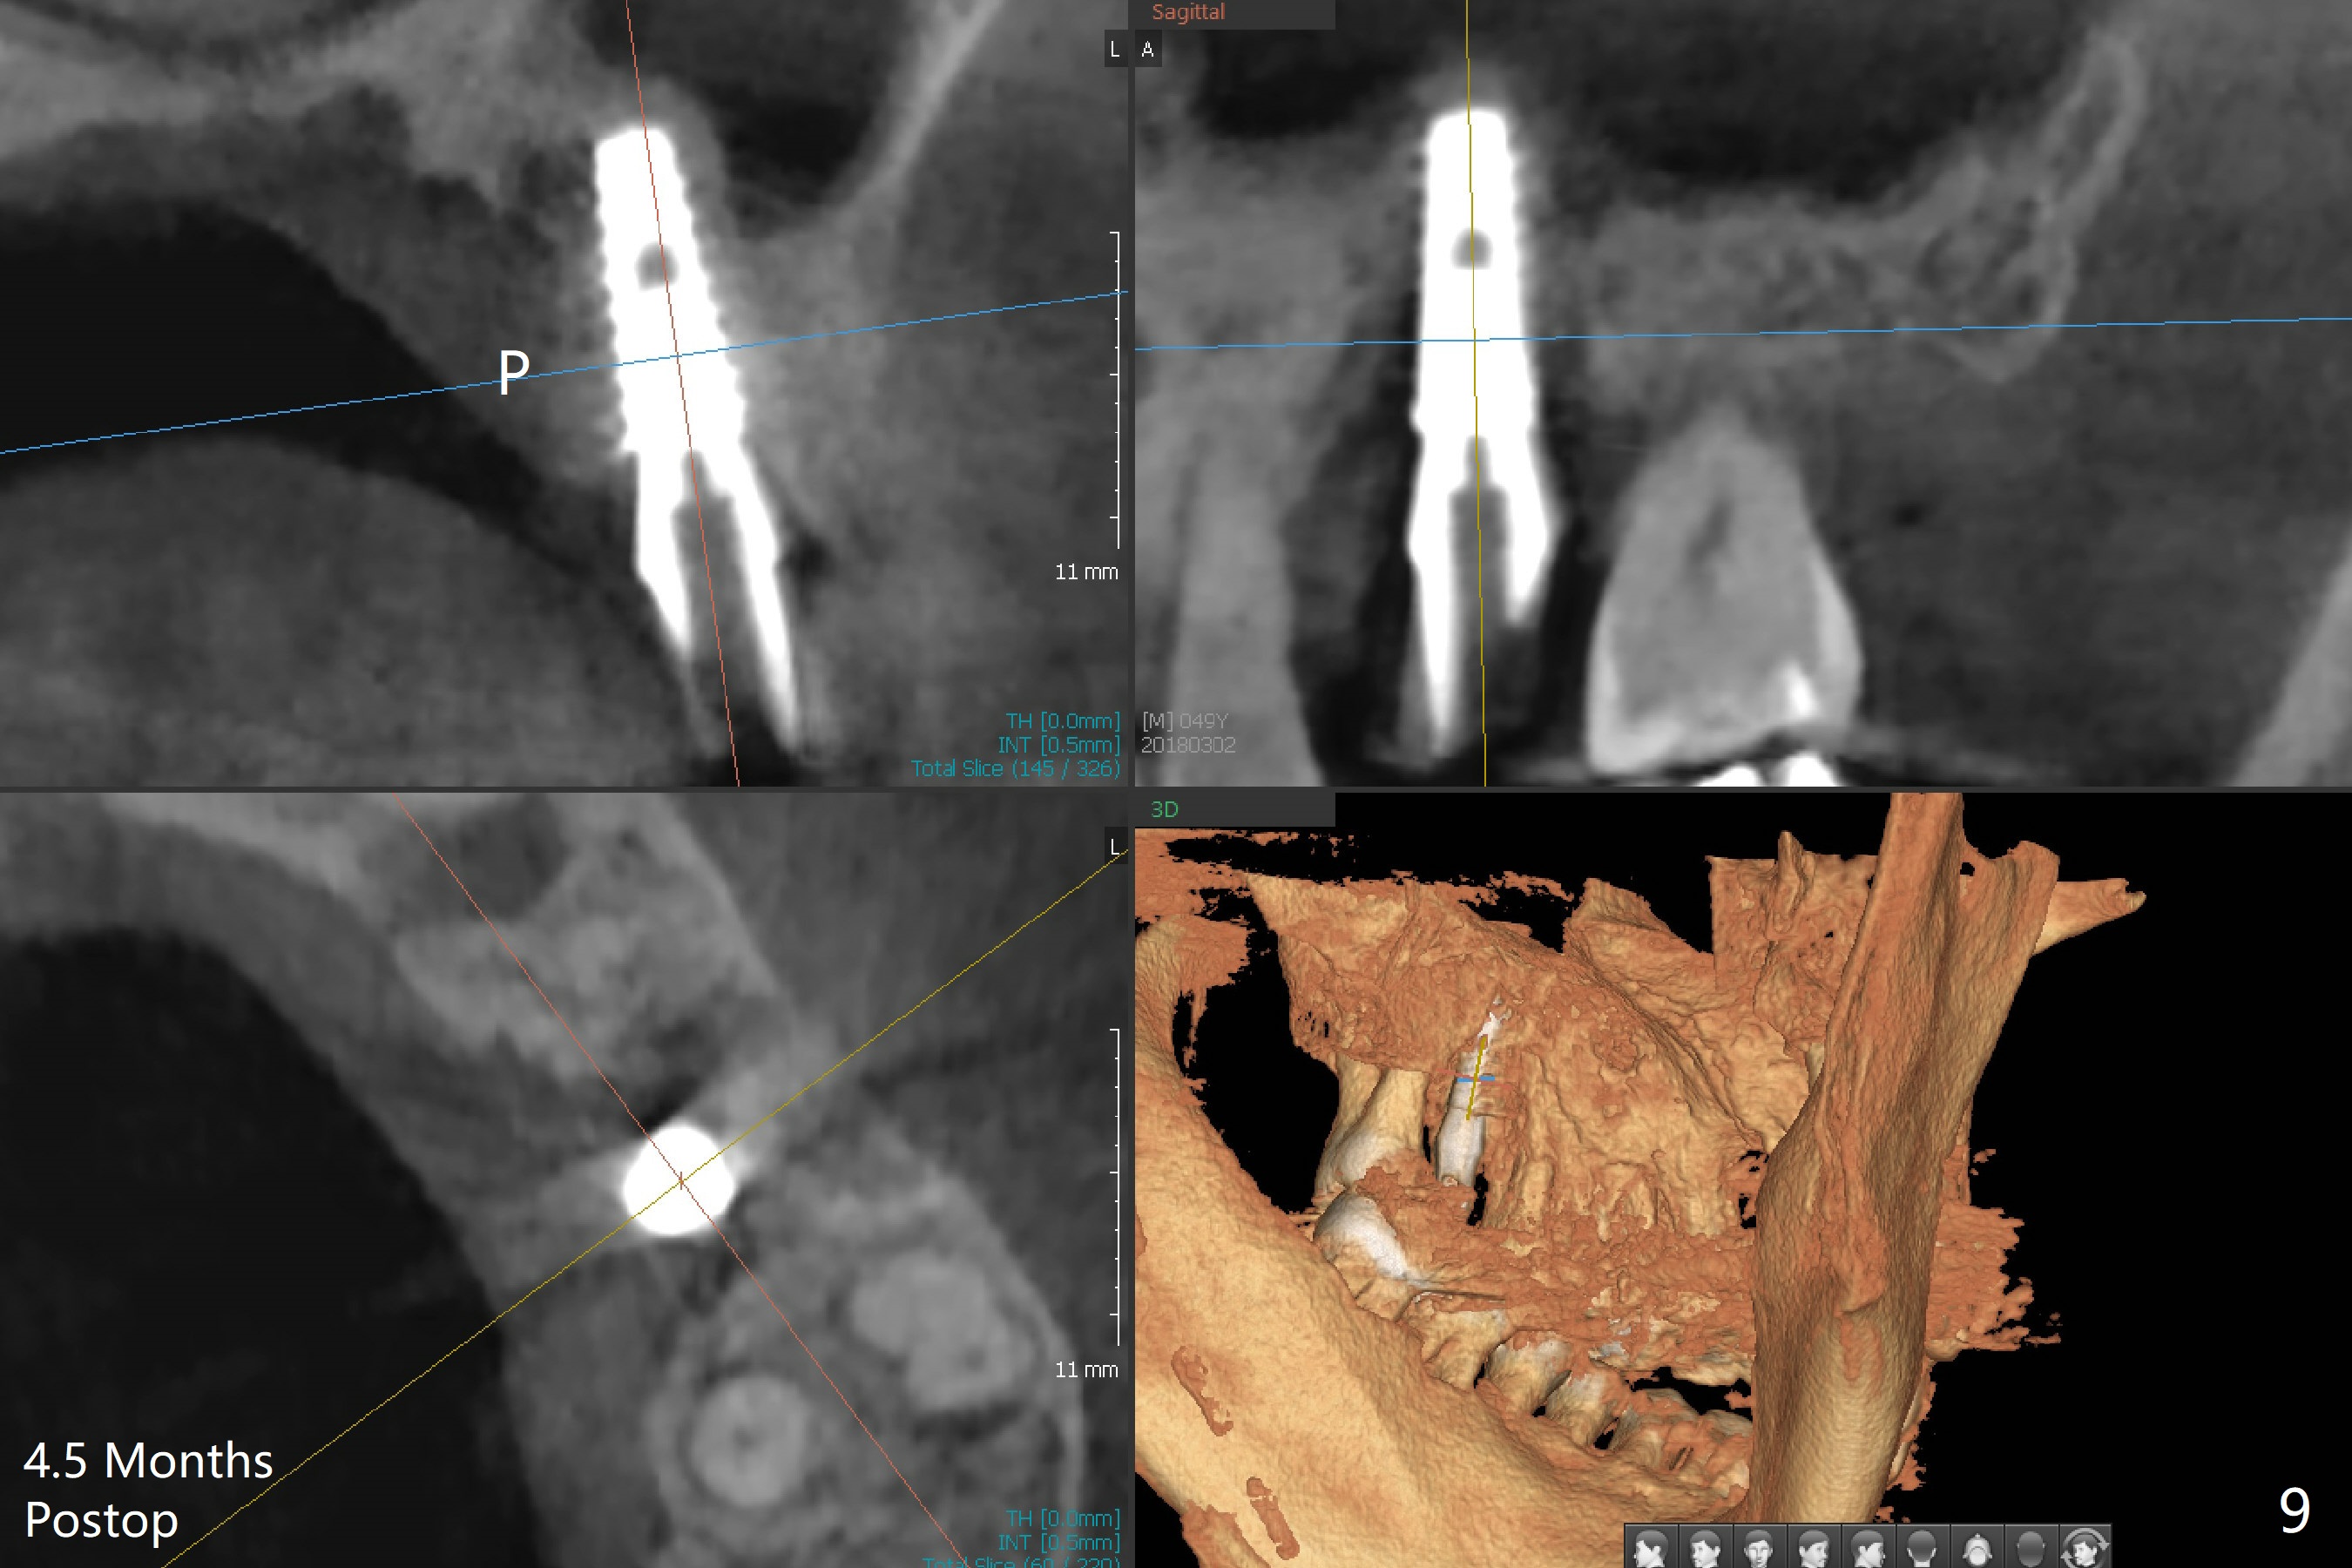

Osteotomy is initiated with Magic Split and 3 mm Magic Expander (ME, flapless) nearly 3 months post socket preservation. To improve the trajectory, the ME is redirected (Fig.1 red line). After use of 3.8 mm ME, Vanilla Graft is placed in the buccal and mesial aspects of the osteotomy. Following reuse of 3 and 3.8 mm MEs, a 4x11 mm dummy implant is inserted with stability (Fig.2 (*: allograft)). More of allograft is placed prior to placement of 5x11 mm IBS implant (Fig.3,4 (~30 Ncm)). The latter is placed palatal. Last the allograft is placed palatal. A 5x4(2) mm abutment is placed to hold periodontal dressing in place. When the ridge is narrow, the implant should be small; 4 mm probably the most appropriate in this case. There is a buccal gap 2 weeks postop (i.e., after dislodgement of periodontal dressing, Fig.5). The implant and abutment appear to be loose ~ 1.5 months postop. The pair abutment is changed to a healing one (5x3mm). The implant seems to be osteotointegrated 3.5 months posotp (Fig.6). Because of the mesial shift of the tooth #15 (Fig.6 arrow (6 months post #14 extraction; anterior open bite)), an angled abutment (5x4mm, 15 degree) is used (Fig.7). Limited orthodontic treatment has to be initiated because the mesially shifted #15 has no occlusal contact mesially (Fig.7 *). A provisional is fabricated with light supra-occlusion. A separator is placed between #14 and 15. Once a space is created in a week, acrylic is added to the distal surface of the provisional and the separator is re-used. In fact the implant is found to be unstable 4.5 months postop (Fig.8,9). The palatal (P) plate is thin and incomplete. The provisional is reduced infraocclusal. Two months the implant remains unstable and is removed.